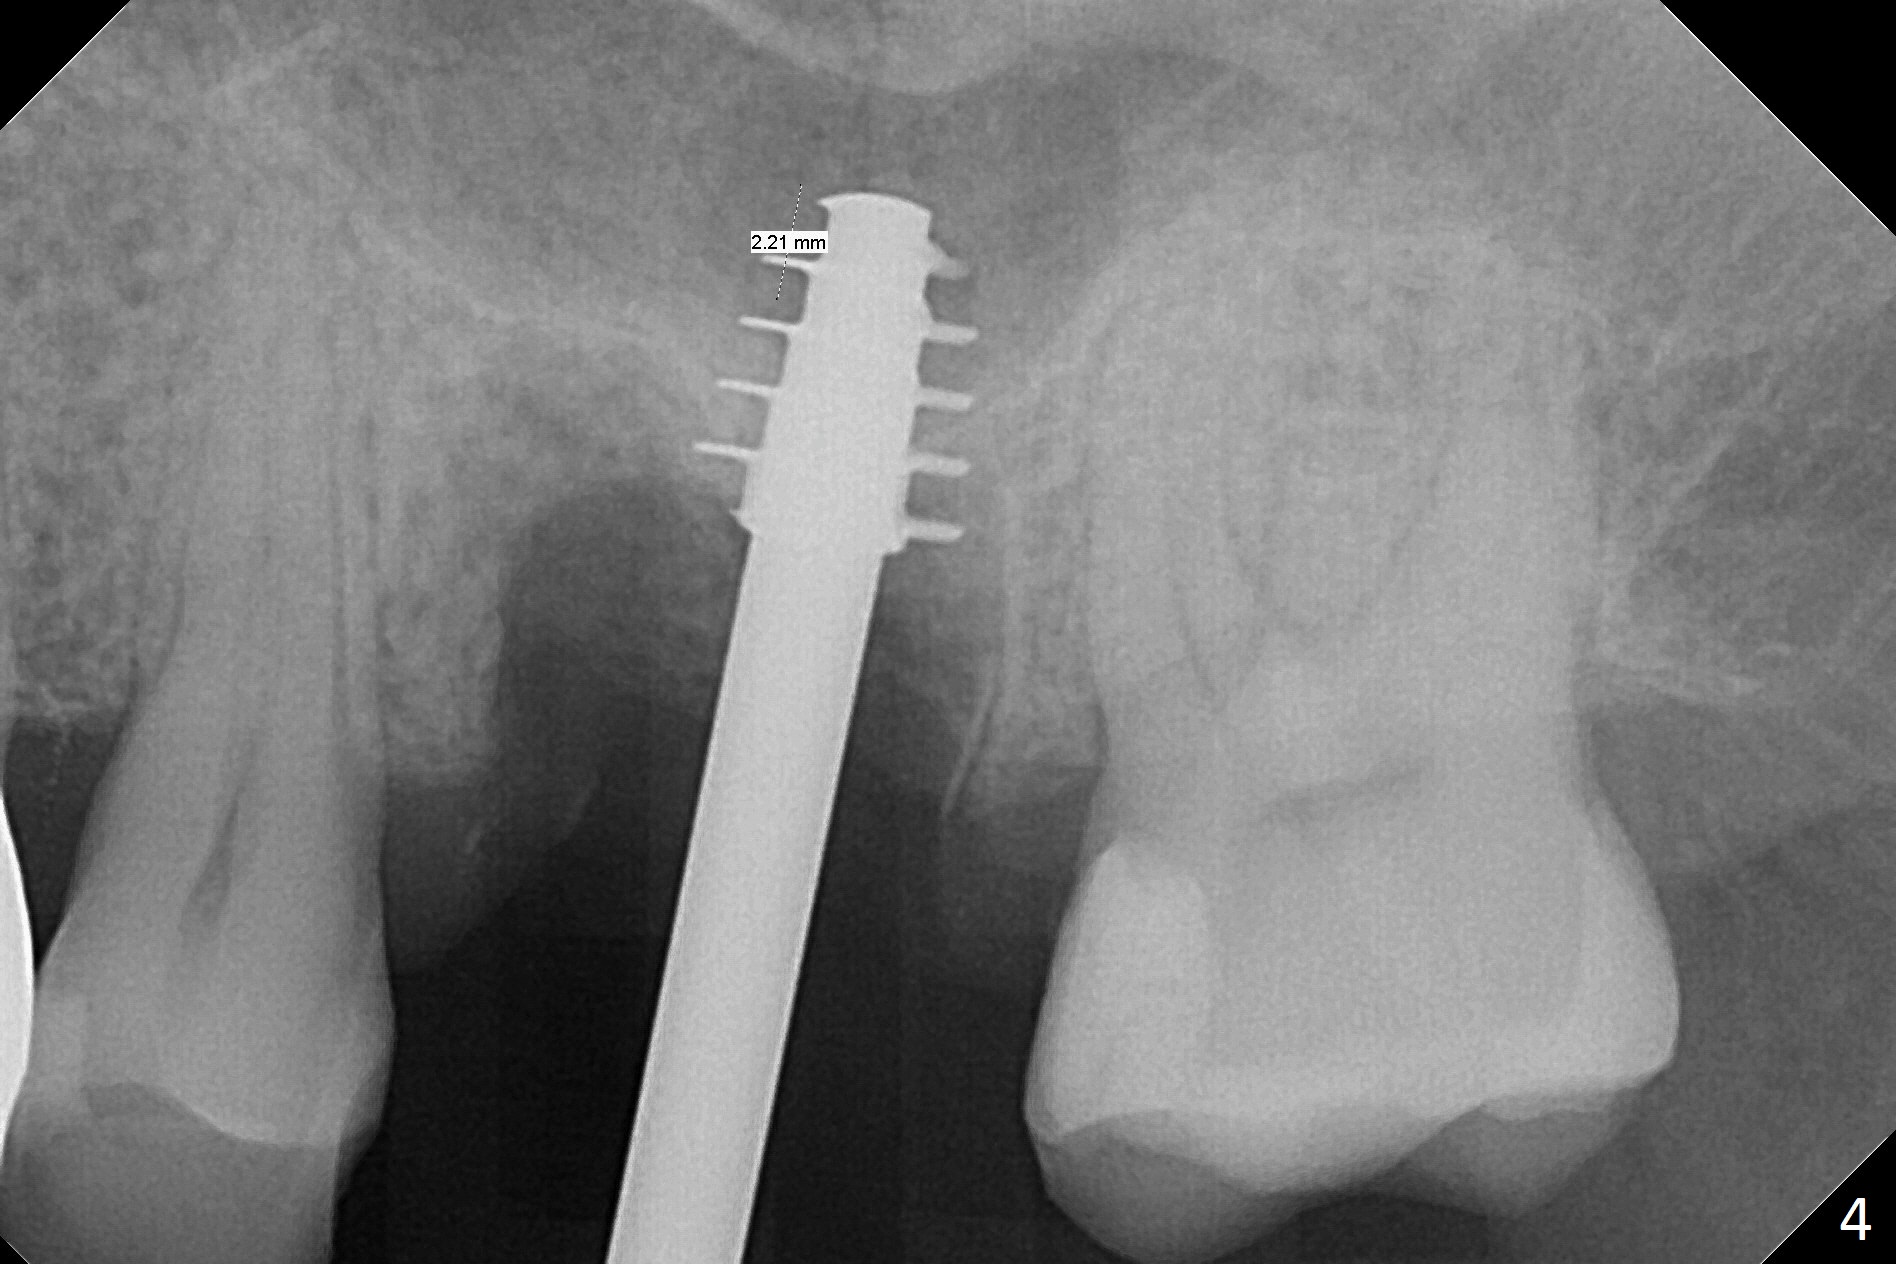

What is unclear preop is the large periapical radiolucency (Fig.1 red dashed line) of the palatal root (P) of the tooth #14. When the tooth is extracted, it is difficult to remove granulation tissue from the palatal apical socket, which is enlarged (Fig.2 (impression of sockets),3). The small dimension of the septum (~4x5 mm (Fig.1 pink) is also unrecognized preop, which leads to sinus perforation when 4.8 mm Magic Drill is used. In spite of use of PRF plug and membrane, allograft does not stay in the osteotomy after placement of 4x11 mm dummy implant or 5 mm tap drill (Fig.4 for 9 mm). Finally a 5.5x7 mm IBS implant is placed with 30 Ncm (Fig.5). After placement of Osteogen plug in the apical portion of the sockets, allograft/Osteogen is placed in the remaining sockets (Fig. 5 *). The latter is partially contained by a 6.5x4(3) mm abutment (A) and ultimately by an immediate provisional.